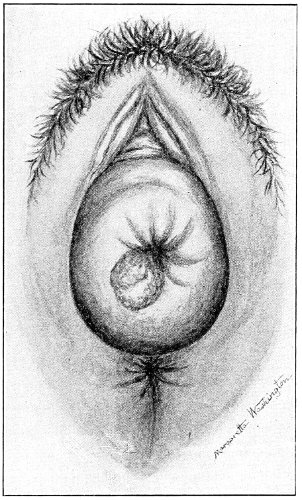

Fig. 16.—Appearance of the external genitals in a woman with gonorrhea: G. m., gonorrheal macula situated at the base of a vaginal caruncle.

Suppuration of the duct may be demonstrated by pressing over the course of the duct, when a drop of pus will escape from the opening. In such cases the orifice of the duct is usually surrounded by a red areola, resembling a flea-bite, which has been called the gonorrheal macula (Fig. 16). This macula persists long after all other traces of inflammation about the vulva and vagina have disappeared, and after all frank suppuration in the duct has subsided. Its presence indicates at least the probability of previous gonorrheal infection.

When the duct of the gland alone is the seat of inflammation, it should be laid open with fine scissors or knife, and the tract thoroughly cauterized with the nitrate-of-silver stick, pure carbolic acid, or a solution of chloride of zinc (2 per cent.).

Suppuration of the vulvo-vaginal gland is accompanied by marked swelling and peripheral edema. The swelling may extend to the anus, and is of characteristic shape (Fig. 17). The pain is always severe. Fluctuation is first apparent on the inner surface of the labium majus. If the condition is not treated, one or more fistulous openings appear below the orifice of the duct, and the pus is discharged. The condition then becomes chronic. The fistulous openings persist. Acute inflammation disappears from the gland, leaving it in a condition of hypertrophic induration. A thin, milky or greenish, purulent fluid may be pressed out of the duct or the fistulous openings. Infection from this discharge may be communicated to man, or may ascend the genital 40 tract, producing inflammation of the endometrium or of the Fallopian tubes.